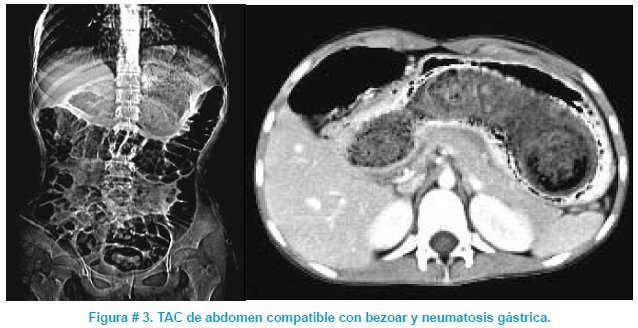

Paciente femenino de 13 años de edad, quien consulta por dolor abdominal, pérdida de peso y vómitos persistentes de tres semanas de evolución. Al examen físico destaca: emaciación, marcada palidez mucotegumemtaria y masa abdominal de 10 cm de diámetro en epigastrio, no dolorosa, fija y adherida a planos profundos. Los exámenes complementarios demostraron: anemia severa, hipoproteinemia e hipoalbuminemia, hierro sérico bajo y TIBC elevado, PPD negativo, marcadores tumorales negativos, ultrasonografía abdominal no concluyente, radiografía de abdomen con medio de contraste sugerente de tricobezoar y la tomografía axial computarizada (TAC) de abdomen fue compatible con bezoar y neumatosis gastroduodenal. Se realizó tratamiento multidisciplinario: transfusión de hemoderivados, manejo nutricional, suplemento con hierro, resolución quirúrgica del tricobezoar, apoyo psicológico y terapia psiquiátrica. Cabe hacer notar que tanto la familia como la paciente, negaron tricotilomanía y la misma que fue aceptada únicamente luego de haber visto el tumor extraído; indicando que la tricofagía tenía varios años de evolución produciendo el deterioro progresivo del estado general. Ver figuras # 1, 2 y 3.